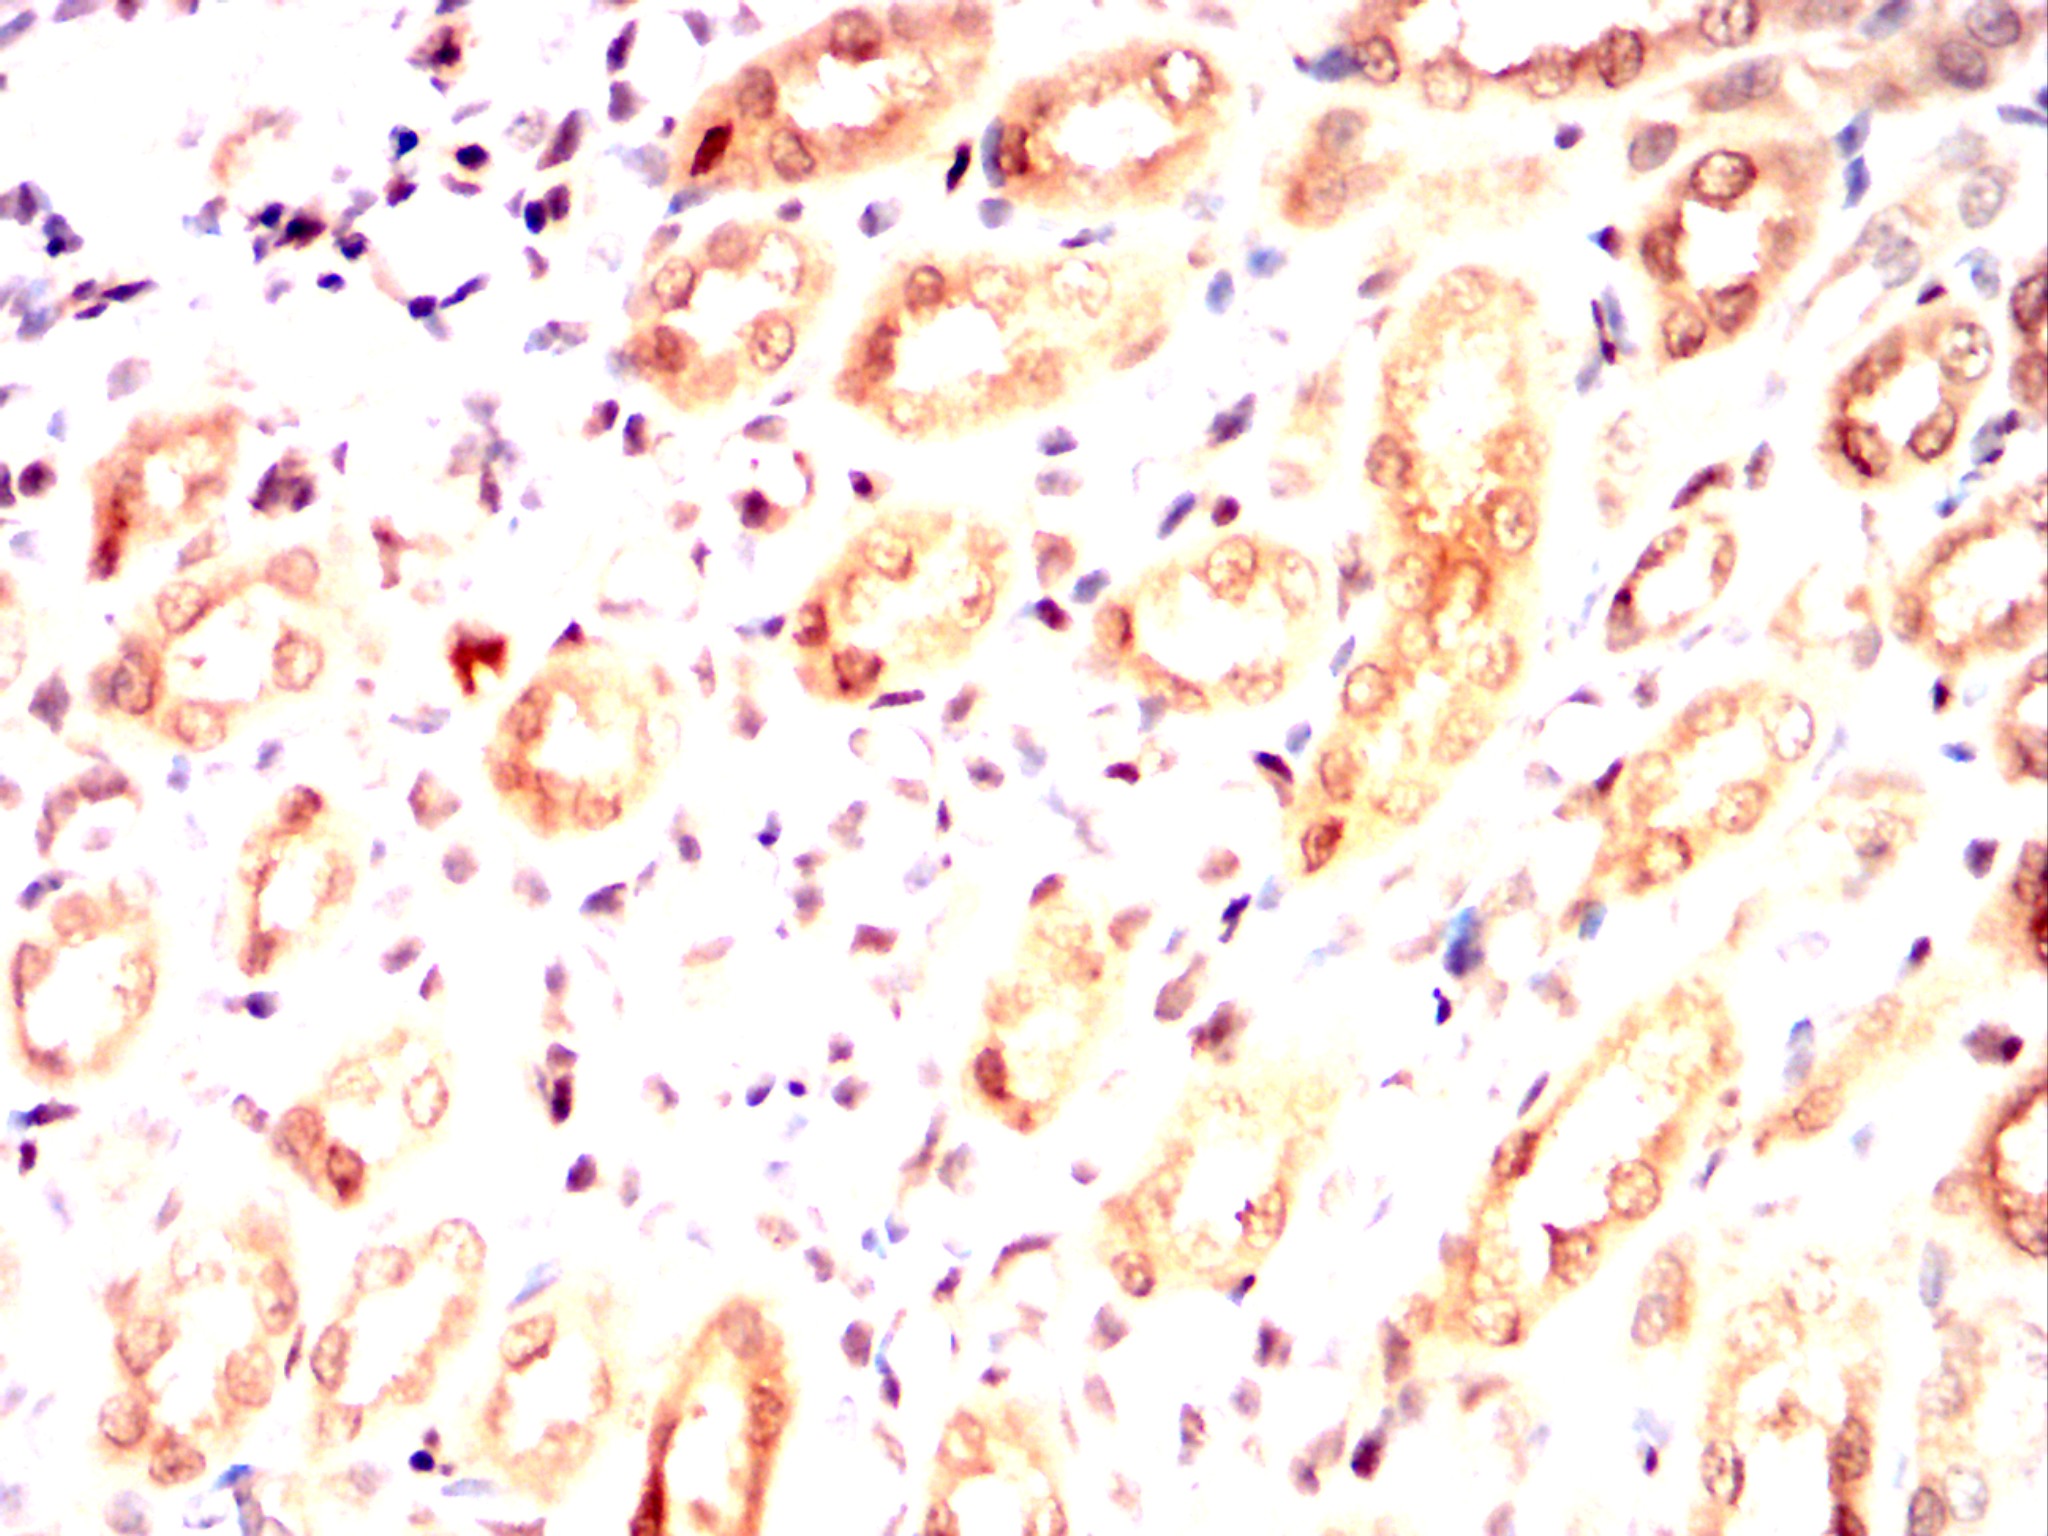

Immunohistochemical analysis of paraffin-embedded Mouse kidney using IRAK4 mouse mAb with DAB staining.

Immunohistochemical analysis of paraffin-embedded Rat kidney using IRAK4 mouse mAb with DAB staining.